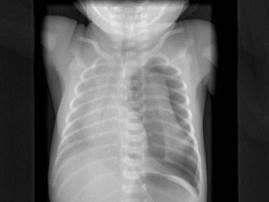

出生一天的早产儿,呼吸窘迫,请结合图片选出最可能的诊断 ( )A、肺气肿B、气胸C、肺气肿D、肋骨骨折E、湿肺

问题 出生一天的早产儿,呼吸窘迫,请结合图片选出最可能的诊断 ( )

选项 A、肺气肿 B、气胸 C、肺气肿 D、肋骨骨折 E、湿肺

答案 B